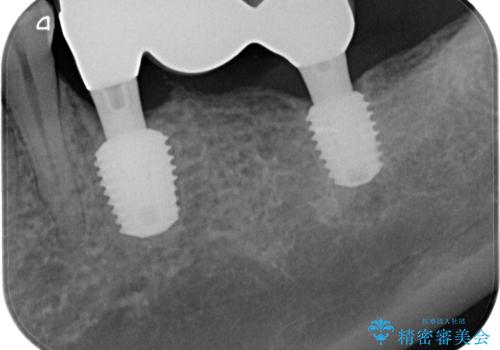

左右ともにインプラントが必要な状態でした。

左下小臼歯は根管治療で対応する予定でしたが、診断のために歯肉を開いたところ頬側に垂直破折が認められたため、抜歯即時埋入インプラントによる補綴治療を選択することとしました。

右下は大臼歯部の歯は抜歯即時埋入インプラントにて、手前の歯は保存して補綴治療を行うこととしました。